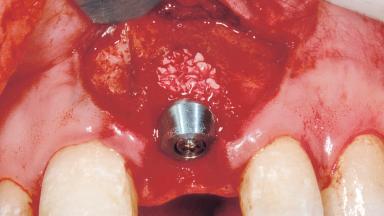

Bone Augmentation Horizontal|Simultaneous

Augmentation Materials Xenogenous|Membrane

Placement Protocol Immediate implant placement

Socket Integrity Damage to one or more bone walls

Bone Volume Damage to one or more socket walls